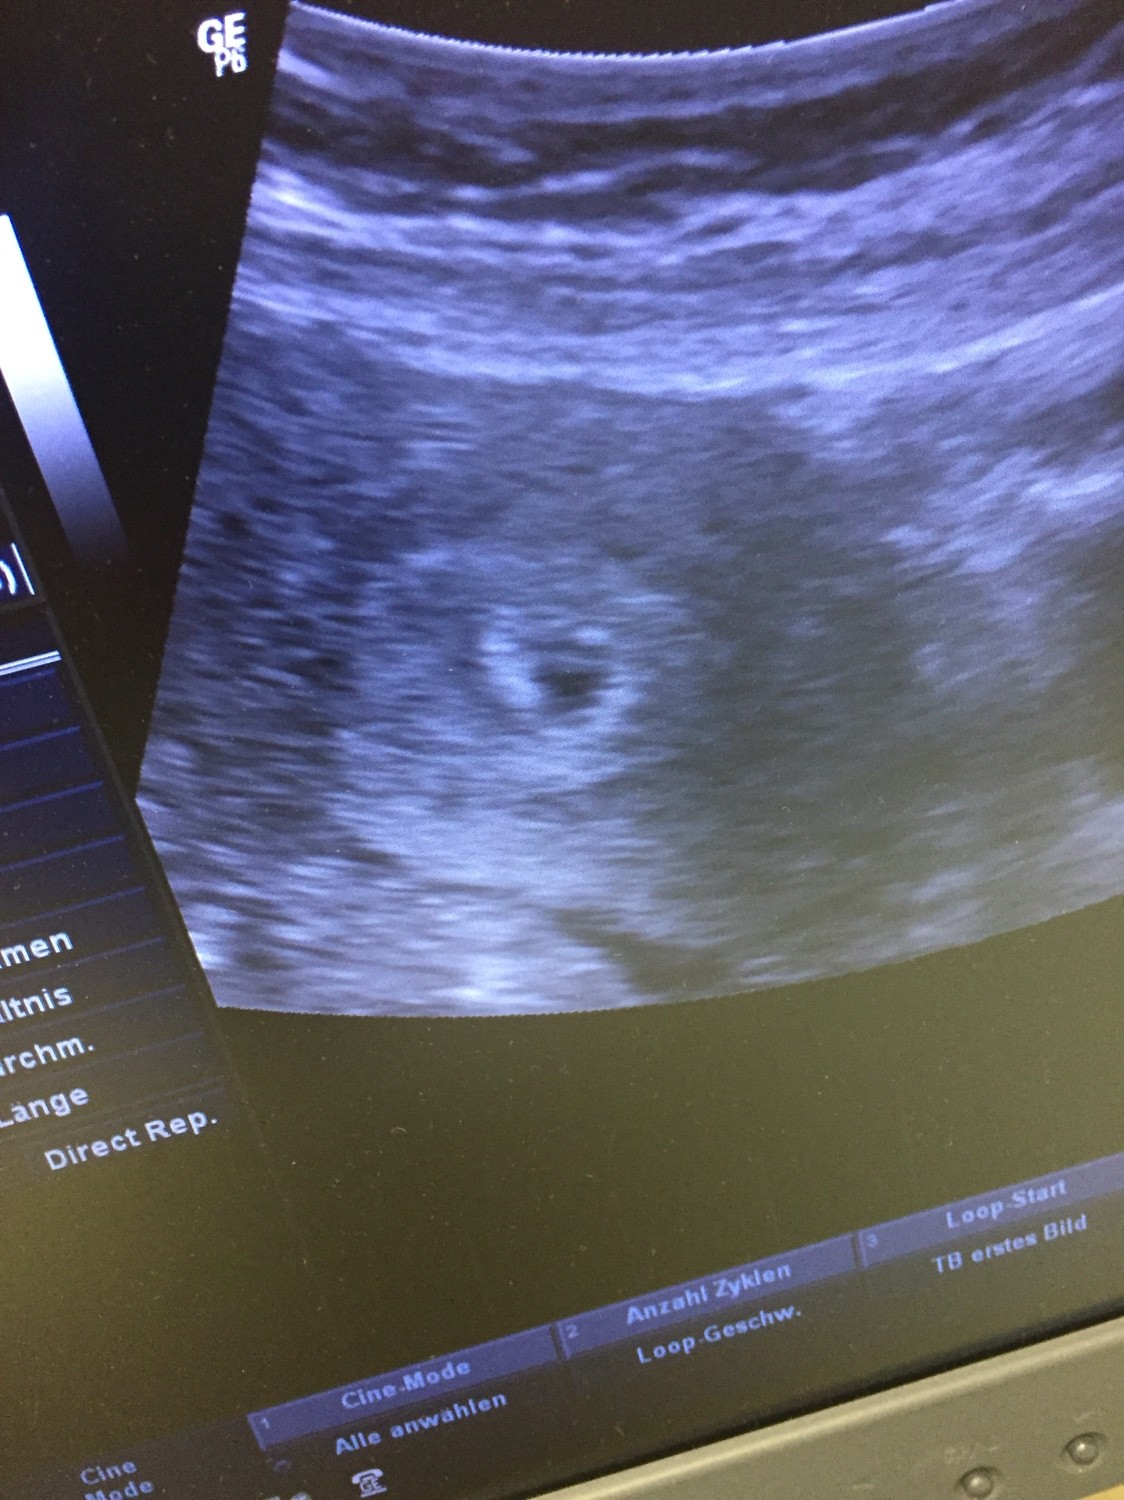

kochane ... moja beta znowu pozytywna trzymajcie prosze kciuki zeby tym razem wszystko bylo dobrze![]()